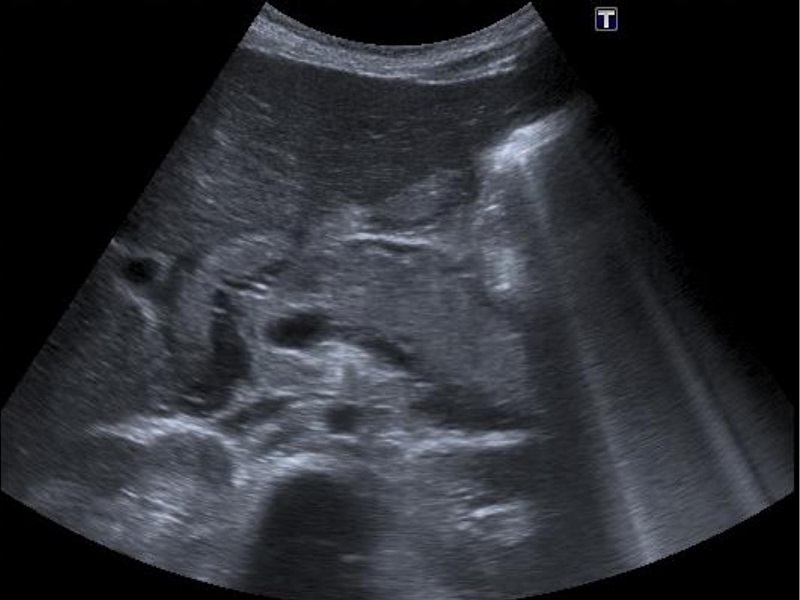

Ecografía abdominal: aumento de tamaño del pácreas con ecogenicidad aumentada y ecoestructura heterogénea con líquido libre peripancreático, periduodenal y saco menor. El resto es normal.

En la ecografía de abdomen se objetiva aumento de tamaño del páncreas con ecogenicidad aumentada y ecoestructura heterogénea con líquido libre peripancreático, periduodenal y saco menor. Resto normal.